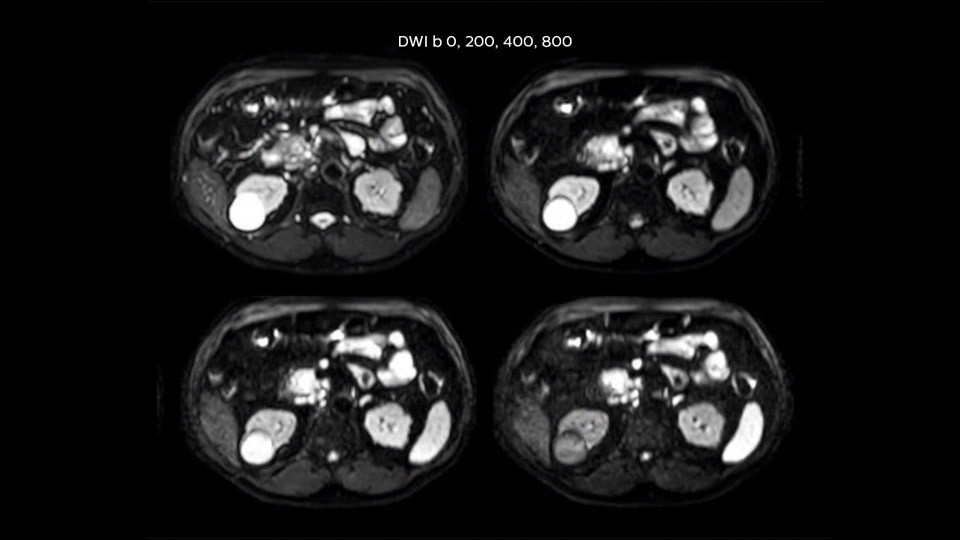

“Our liver exams are quite fast,” says Dr. Baumann. “If the patient tolerates it, we use an arms-up position to reduce the FOV and speed up the exam with dS SENSE.” “We acquire one transversal high resolution T2-weighted sequence with 3 mm slice thickness, for example for pancreas or liver lesions. Then we also add a T2 fat suppressed MultiVane XD SPIR sequence. We perform these two routinely in our liver imaging. We use high dS SENSE factors to significantly shorten scan times to 2-4 minutes, which can improve our protocol; it’s a very robust scan.” “We include mDIXON for the dynamic sequences because of the robust and homogeneous fat suppression we get with that. We had been using eTHRIVE, but we are now quite happy with mDIXON. Sometimes we use a medication to calm the bowels, to further improve the image quality.”